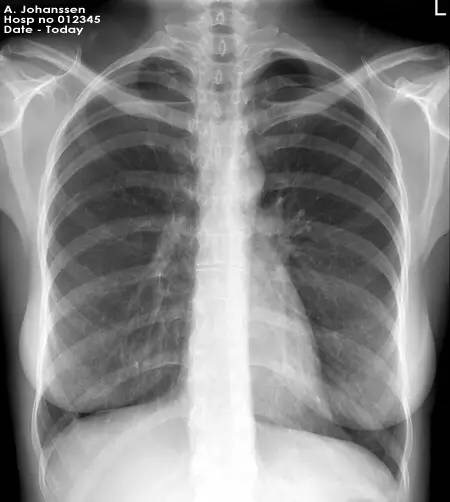

根据美国放射协会和妇产协会的数据,孕妇接受单次胸部x线检查腹中胎儿受到的照射剂量为0.02–0.07毫rad。记住,高于5000毫rad才会造成胎儿损伤。单次腹部x线平片胎儿受到的照射量为100毫rad,肾盂静脉造影胎儿受到的照射量可能大于1rad。乳腺钼靶检查胎儿受到的照射量为7-20毫rad。钡灌肠或者小肠连续成像检查胎儿受到的照射量可以达到2-4rad。头胸部CT检查胎儿受到的照射量小于1rad。腹部或者腰椎CT扫描胎儿受到的照射可以达到3.5rad。

也就是说,普通x线平片通常只会暴露胎儿于非常小的照射剂量。而且通常孕期需要做x线检查时候,孕妇的腹部是会用含有铅的防护衣保护起来的,更进一步降低受照剂量。除开钡灌肠和小肠连续成像,绝大多数造影剂荧光检查也只会给胎儿带来毫rad的剂量。CT造成的照射依照射数量和成片距离会有不同。盆腔CT可能会给胎儿带来高达1.5rad的照射,但放射科医生通过使用低剂量技能是可以将它降低到接近250毫rad的。

常规齿科x线检查,头部x线检查,四肢x线检查,以及胸部x线检查,包括乳腺钼靶检查,或者头胸部CT是不会对胎儿造成损伤的,儿童期癌症的风险提高也可以忽略不计。需要做腹部检查时请与医生商量。所以如果孕期因为疾病的原因,或者受到创伤确实需要做x线检查且没有更佳替代,是不需要因此担心会造成胎儿危险而拒绝检查。你的健康不但对自己,对你的孩子也是较重要的。